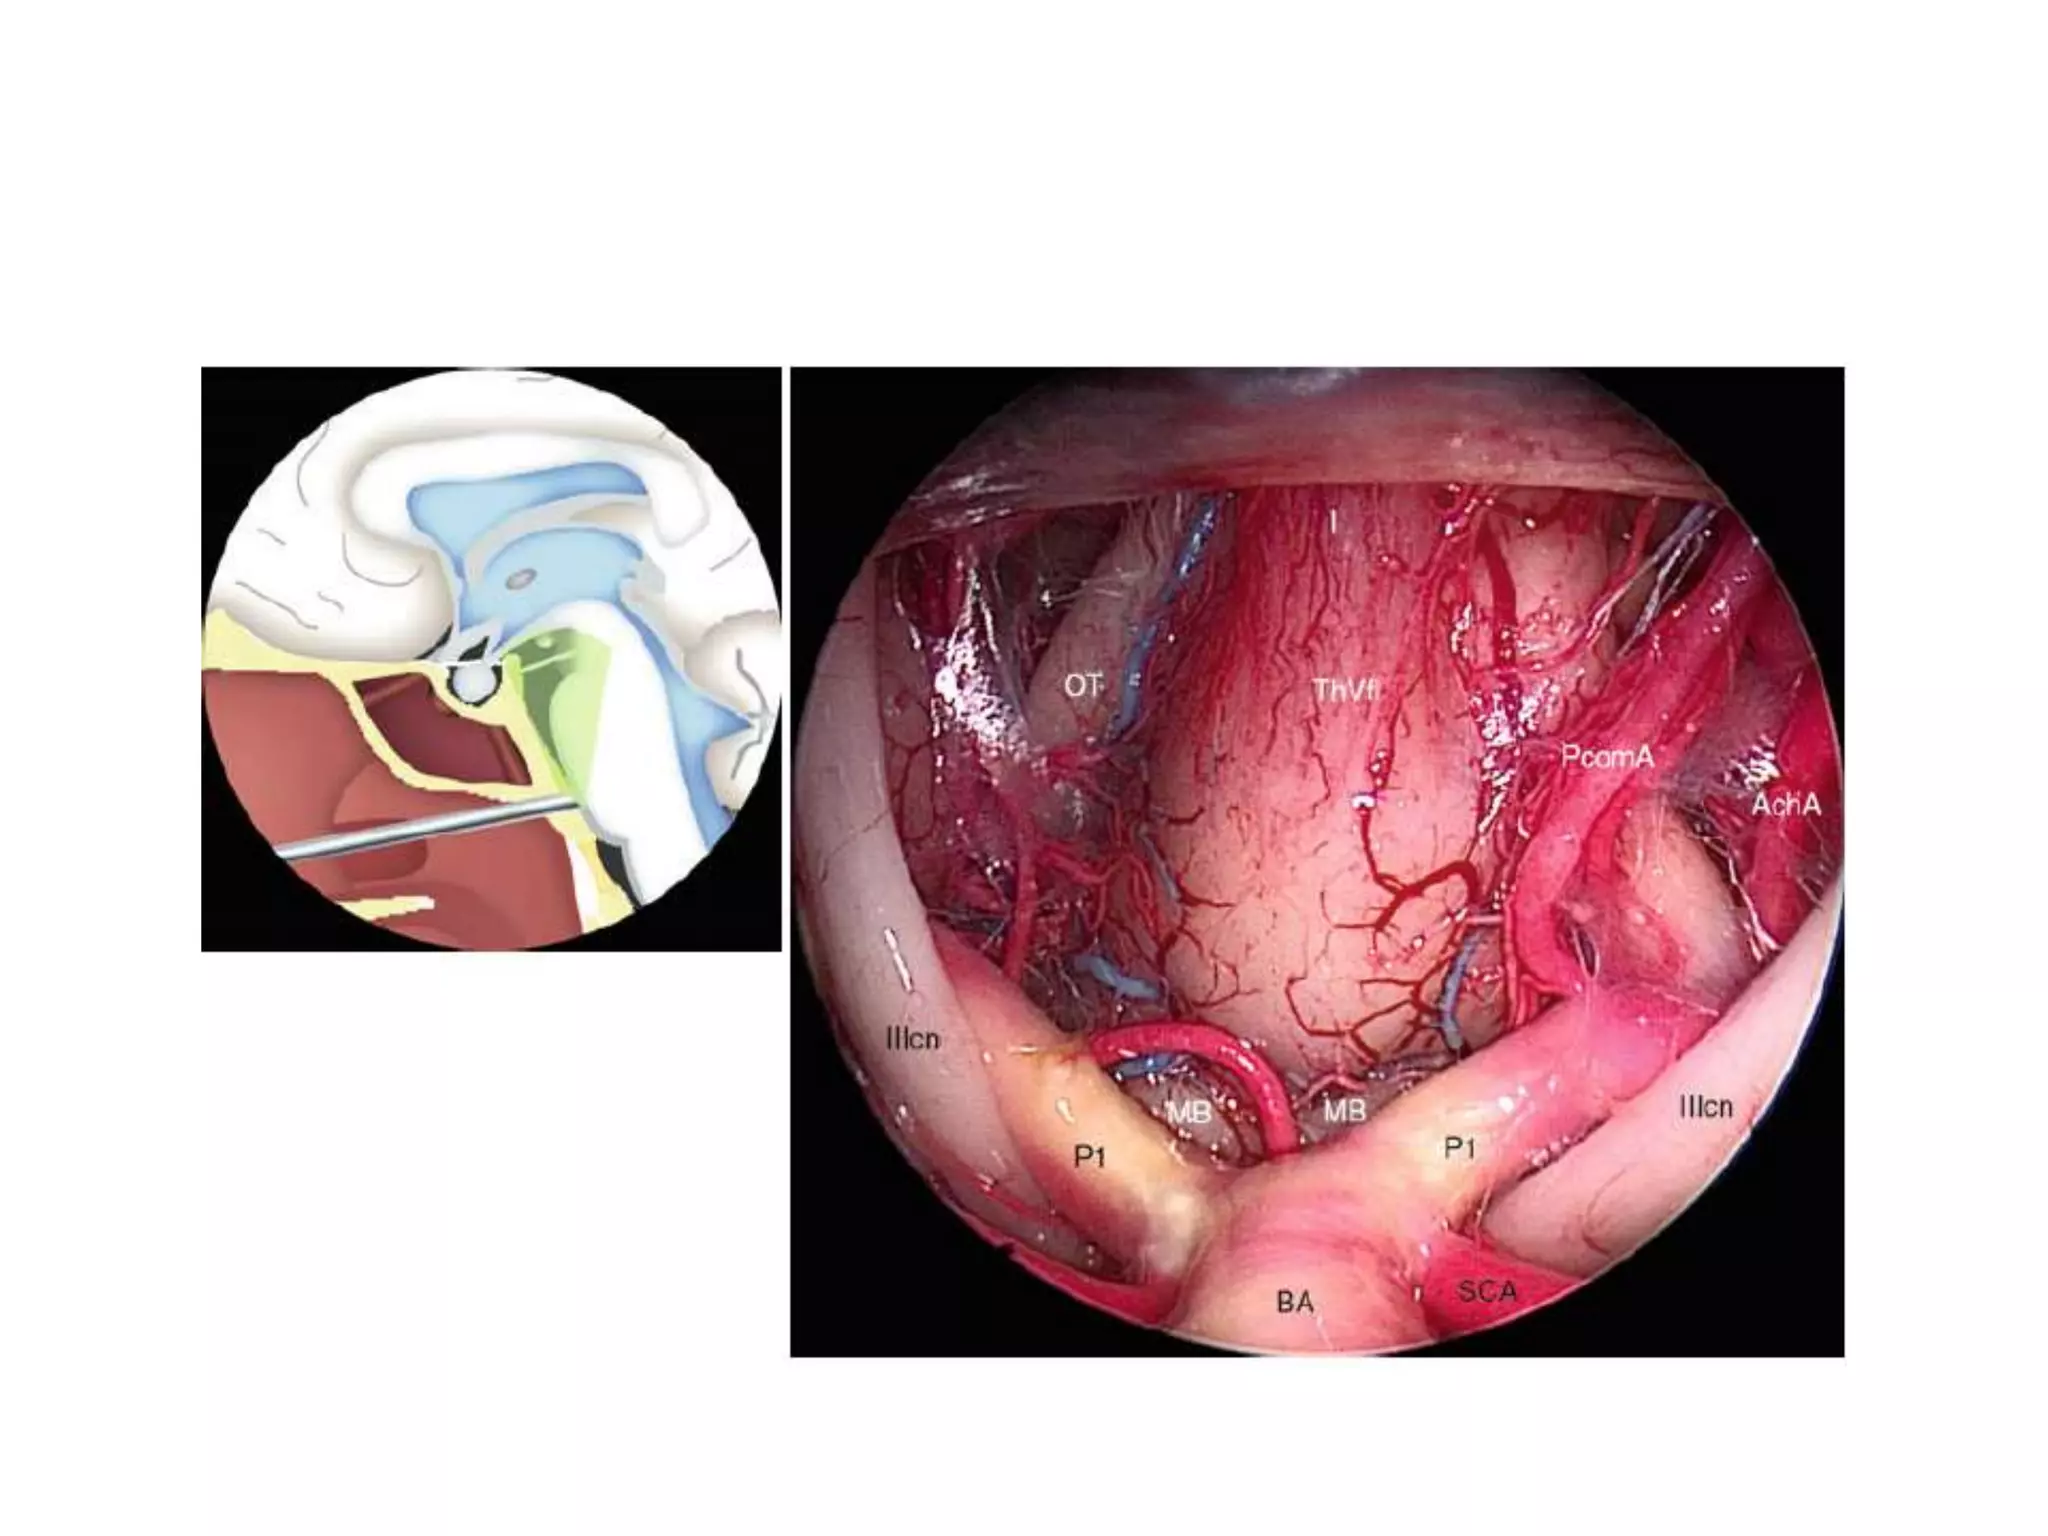

ACA anterior cerebral artery, AchA anterior choroidal artery, BA basilar artery, Cl clivus, DS diaphragma

sellae, ICAi intracranial portion of the internal carotid artery, OA ophthalmic artery, ON optic nerve,

PcomAf posterior communicating artery (fetal configuration), PcomAn posterior communicating artery

(normal configuration), PG pituitary gland, PS pituitary stalk, P1 fi rst segment of the posterior cerebral

artery, SCA superior cerebellar artery, SHAs superior hypophyseal arteries, TS tuberculum sellae, IIIcn

oculomotor nerve

The PcomA is the most variable vessel of Willis’s circle. If PcomA is wider than P1, it is

said to be of the fetal type. This happens in about 20 % of cases. In 1 % of cases, it is

absent (Lang 1995 ) .

PcomAf posterior communicating artery (fetal con fi guration), PcomAn posterior communicating artery

(normal con fi guration), PG pituitary gland, PS pituitary stalk, P1 fi rst segment of the posterior cerebral